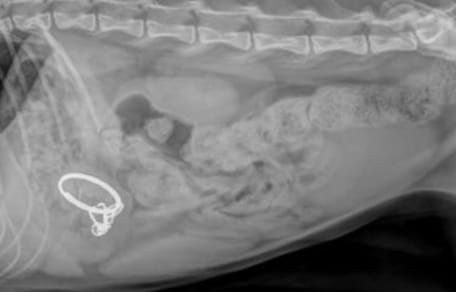

Blumenartiges Gewächs statt verheilter Wunde

Der vereinbarte Termin zur Nachkontrolle nach zwei Wochen wird vom Halter verschoben. Nach etwa drei Wochen taucht er dann doch mitsamt dem Kätzchen wieder in der Praxis auf. Beim Blick auf den Bauch des Tieres, verschlägt es dem Veterinär die Sprache.

Denn anstatt eines kleinen Schnittes, der eigentlich inzwischen problemlos verheilt sein sollte, prangt dort ein regelrechtes Gewächs aus Haut und Fleisch!

„Anscheinend hielt der Besitzer den Einschnitt mit Wasserstoffperoxid ‚sauber‘“, heißt es in dem Facebook-Post zur Erläuterung. Und das ist ein absolutes No-Go.